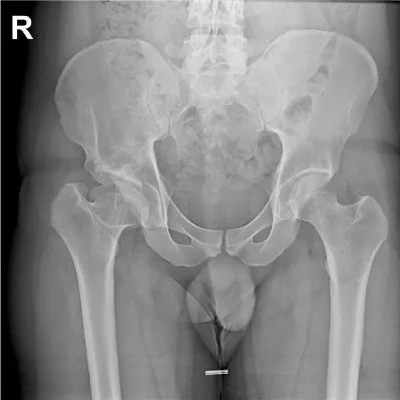

When we suspect a child does have hip issues, often they are referred for X-ray or Ultrasound assessment. Below is an X-ray of normal hip (The side without the R) and a hip with dysplasia (the side with the big R)

Photo source/credit: Radiopedia.